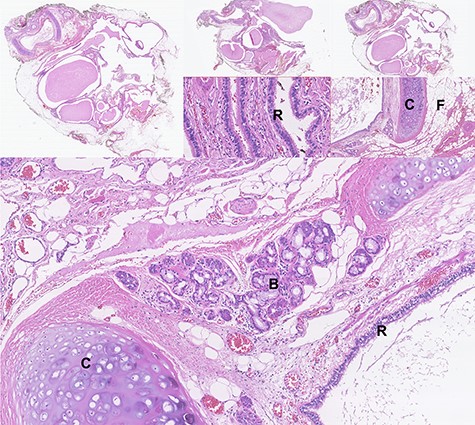

Macroscopically, the specimen consisted of a walled cyst filled with yellowish greasy material measuring 4.5 × 3.5 × 2cm and the left adrenal gland measuring 5 × 3 × 2 cm, both surrounded by adipose tissue. Microscopic evaluation revealed a mature cystic teratoma and a left adrenal gland without morphologic changes (Fig. 5). Neither immature nor malignant components were identified. After 20 months of follow-up, he is free of recurrence.

Photomicrographs of haematoxylin-eosin stained tissue sections showing the microscopic features of the mature cystic teratoma: cystic spaces lined with respiratory epithelium (R), areas of cartilage (C) with mucinous- and serous-type bronchial glands (B), abundant fibroadipose tissue (F), lymphoid structures, smooth muscle, nerve and ganglionic tissue.